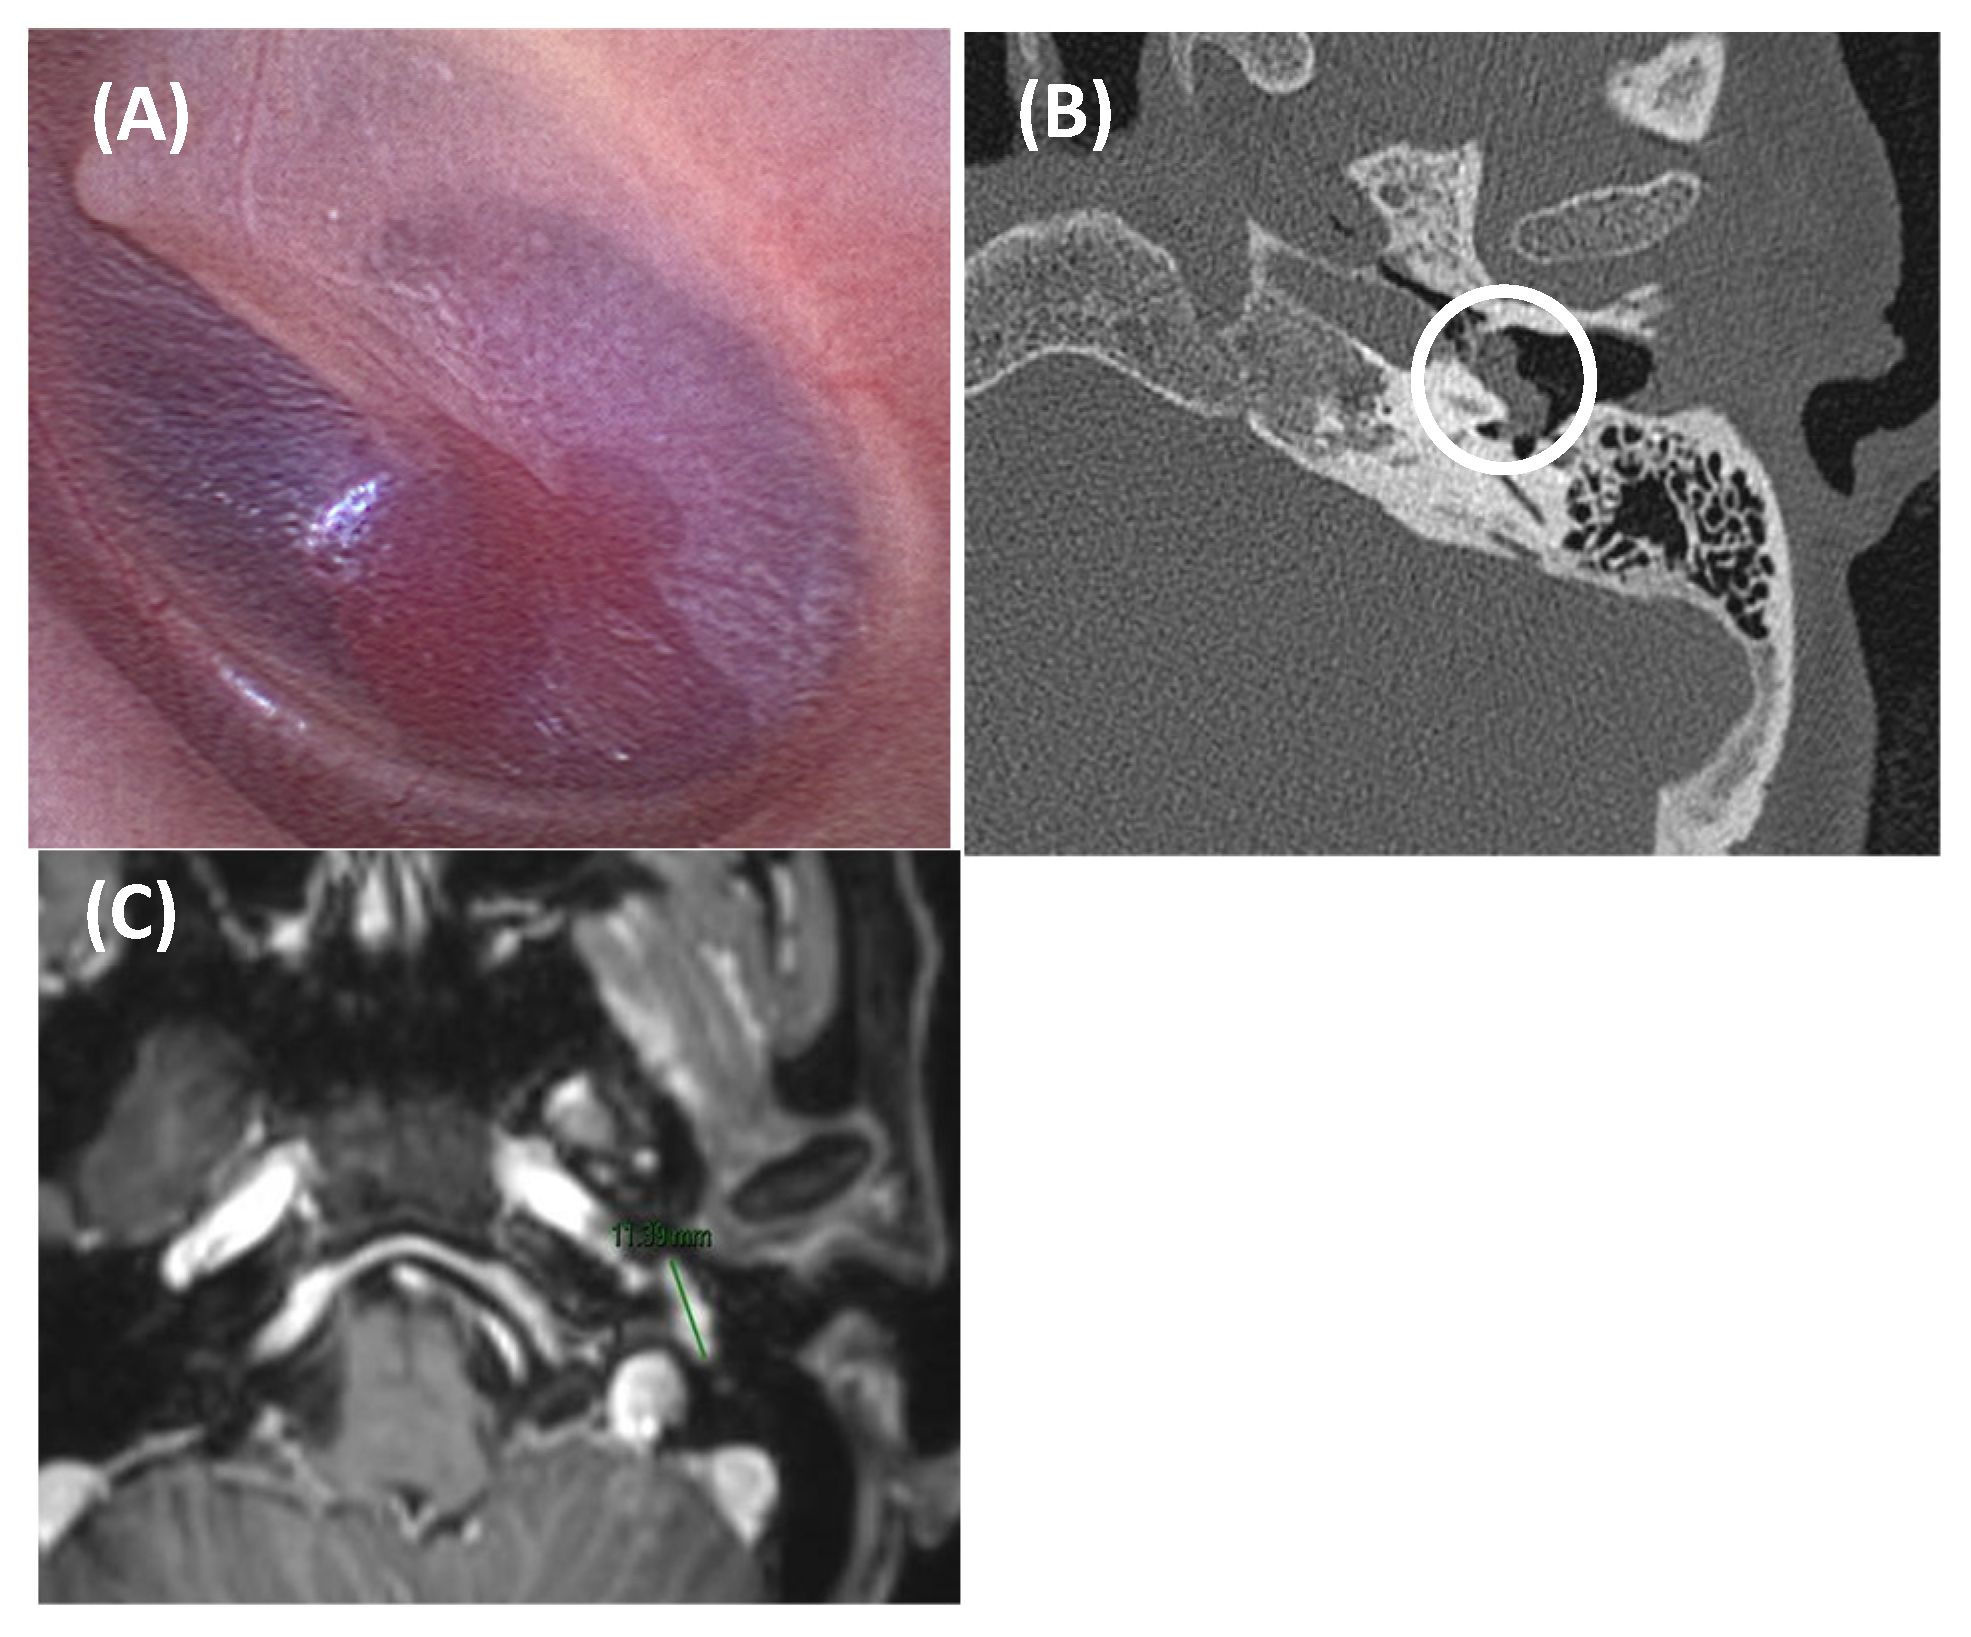

- Aberrant and/or dehiscent ICA

- Lo, W.W.; Solti-Bohman, L.G.; McElveen, J.T., Jr. Aberrant carotid artery: Radiologic diagnosis with emphasis on high-resolution computed tomography. RadioGraphics 1985, 5, 985–993. [Google Scholar] [CrossRef]

| Aberrant and/or dehiscent internal carotid artery Persistent stapedial artery Tympanic/jugular paraganglioma Jugular bulbar abnormalities (high-riding, dehiscence, or diverticulum) |

| Temporal bone abnormalities | Superior semicircular canal dehiscence Otosclerosis Paget’s disease Sigmoid sinus dehiscence/dehiscent jugular bulb Petrous carotid canal dehiscence |

| Aberrant ICA or persistent stapedial artery | +++ | +++ | +++ | - | ± | +++ | - |